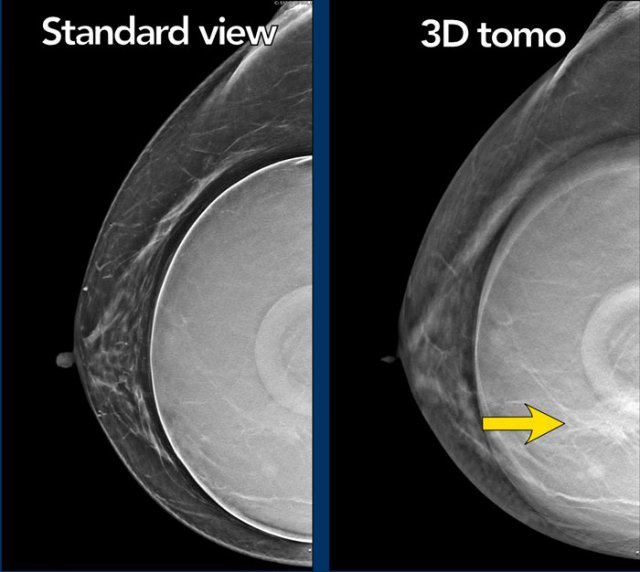

Tomosynthesis

Tomosynthesis can be very useful as in this case.

There is a mass on the lateral side, which is best seen on the 3D tomographic image.

Ultrasound guided biopsy was performed and this mass proved to be a fibroadenoma.

There is a mass, which is more obvious on the tomosynthesis (image 56 out of 73).

It is a spiculated mass.

Pathology: infiltrating lobular carcinoma grade 2 and LCIS.

Another example of the value of tomosynthesis.

The tumor is best seen on the tomographic view.